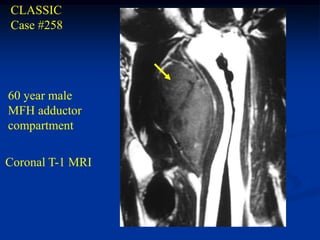

CLASSIC

Case #258

60 year male

MFH adductor

compartment

Coronal T-1 MRI